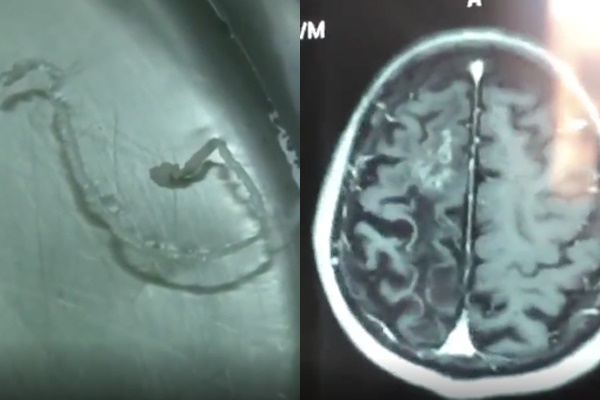

Hình ảnh chụp MRI phát hiện tổn thương trong não (ảnh phải) và hình ảnh con sán ngoe nguẩy được gắp ra

Hình ảnh chụp MRI cho thấy, thuỳ trán phải của ông có các nốt tổn thương. Xét nghiệm máu cho thấy có sự hiện diện của ký sinh trùng. Bác sĩ chỉ định phải phẫu thuật càng sớm càng tốt.

Sau phẫu thuật, các bác sĩ đã gắp ra con sán dài 10 cm, trong suốt và vẫn ngọ nguậy. Sau mổ, bệnh nhân hồi phục nhanh, các cơn đau đầu biến mất.